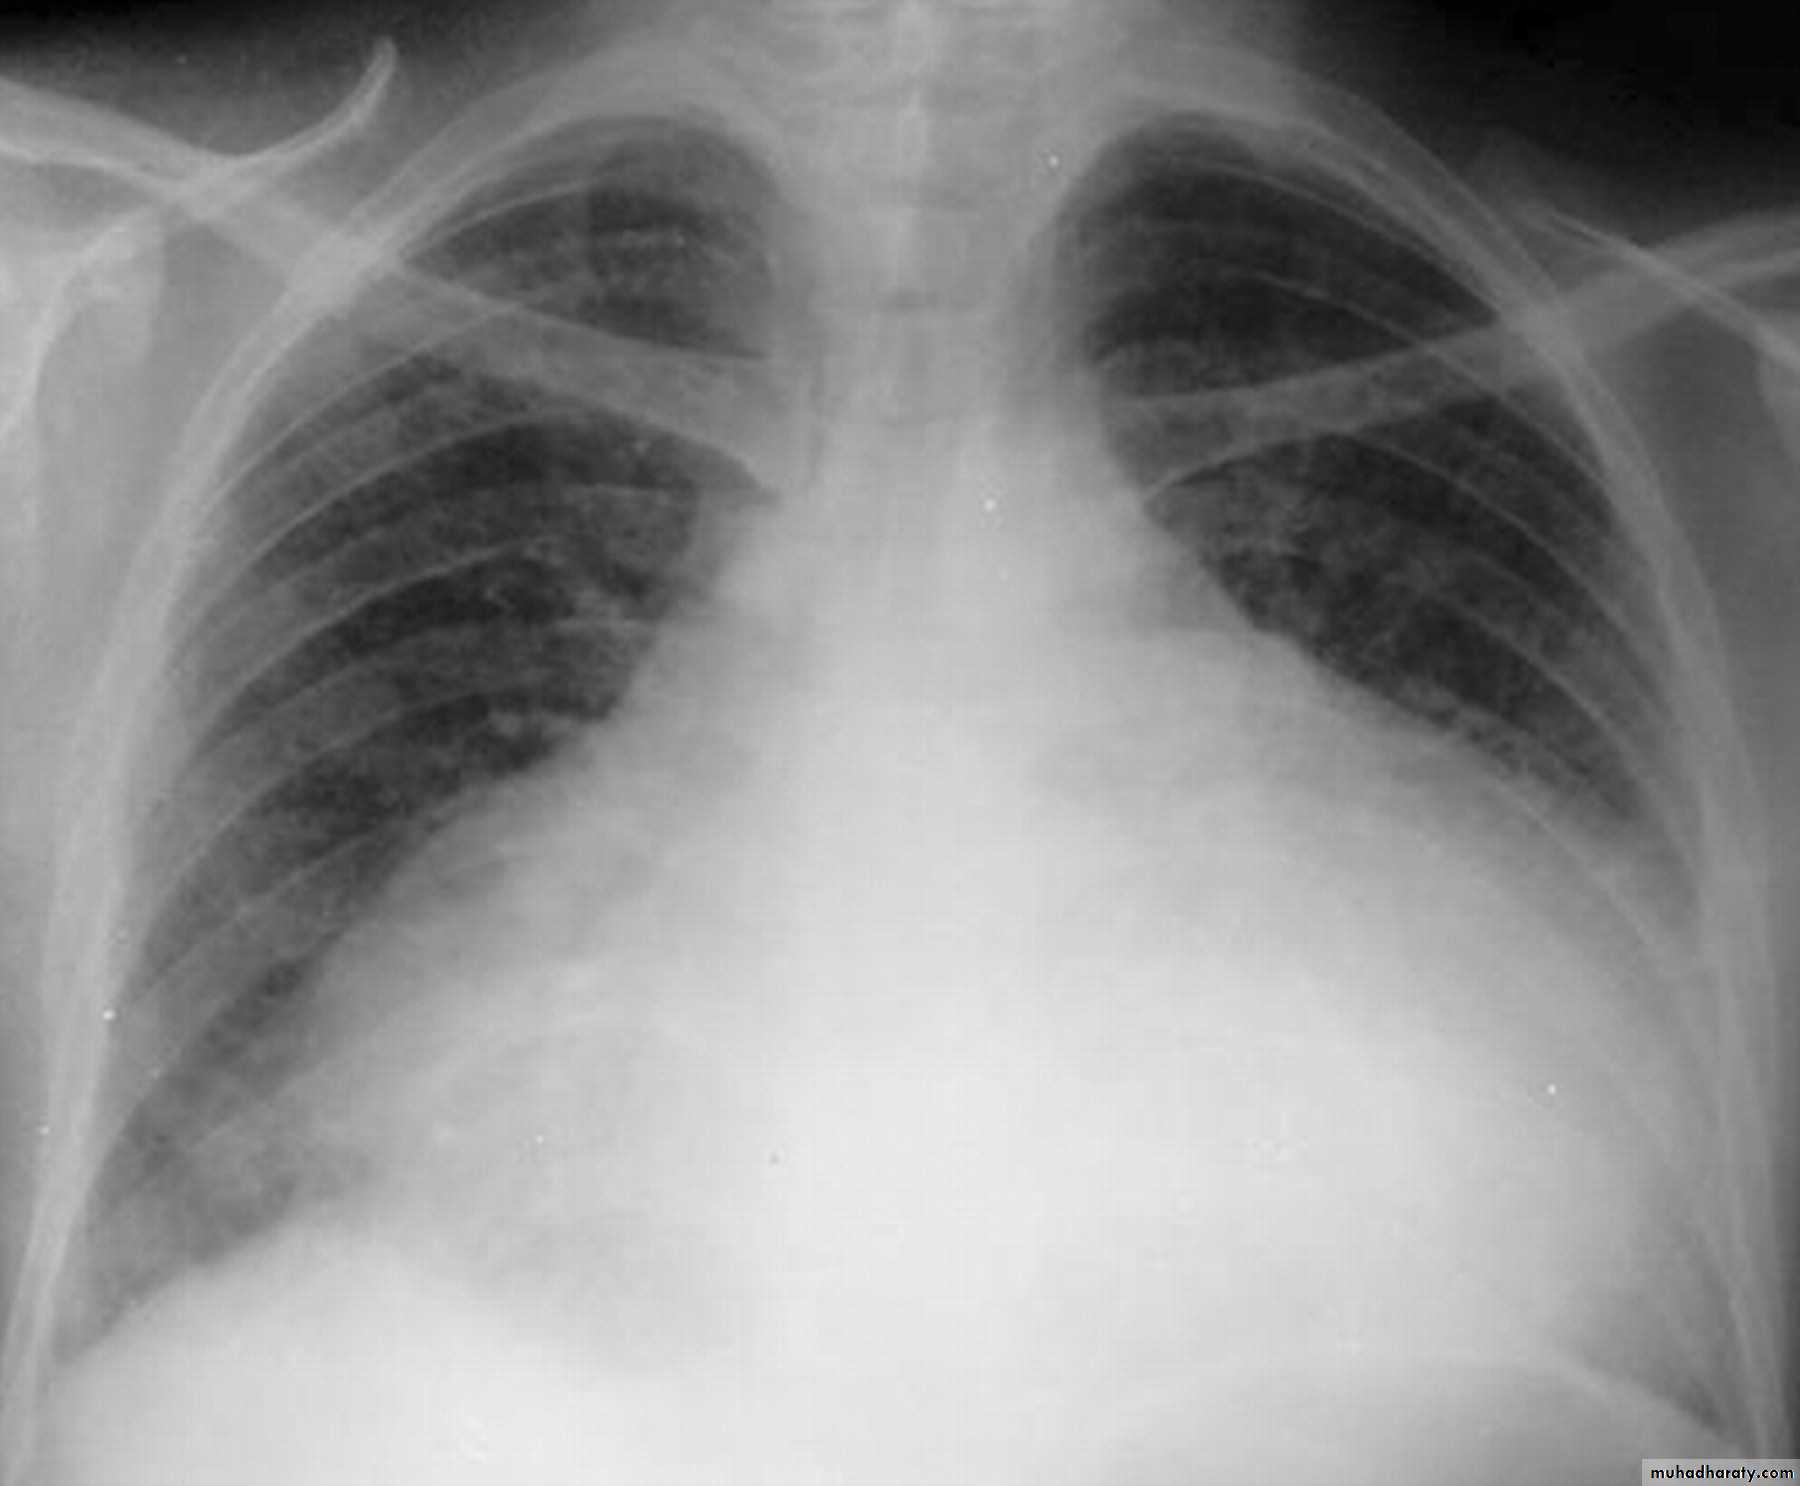

Cardiothoracic ratio (CTR) = Cardiac Width : Thoracic Width

A CTR of greater than 1:2 (50%) is considered abnormal. This however, assumes the projection is Posterior-Anterior (PA), and that cardiac size is not exaggerated by factors such as patient rotation or an incomplete breath in .

The cardiothoracic ratio aids in the detection of cardiomegaly, or more broadly, enlargement of the cardiac silhouette. .

Enlargement of the cardiac silhouette on chest x-ray can be due to a number of causes :

cardiomegaly (most common cause by far)pericardial effusion

anterior mediastinal massprominent epicardial fat pad

Causes of cardiomegalyThere are many etiologies for cardiomegaly. The list includes:*Mitral valve disease

*Congestive heart failure

Congestive cardiac failure (CCF) is a form of cardiac failure which is primarily manifested by the heart inability to pump the volume of blood. It can affect the left (common) or right cardiac chambers or both.

Radiographic features

Chest radiograph

With left sided congestive cardiac failure, the features are that of pulmonary edema which includes:

central pulmonary venous congestion ( prominent hilum )

cephalization of pulmonary veins ( upper lobe pulmonary venous diversion )

pulmonary interstitial edema

pulmonary alveolar edema

Cardiomegaly

Pleural effusion